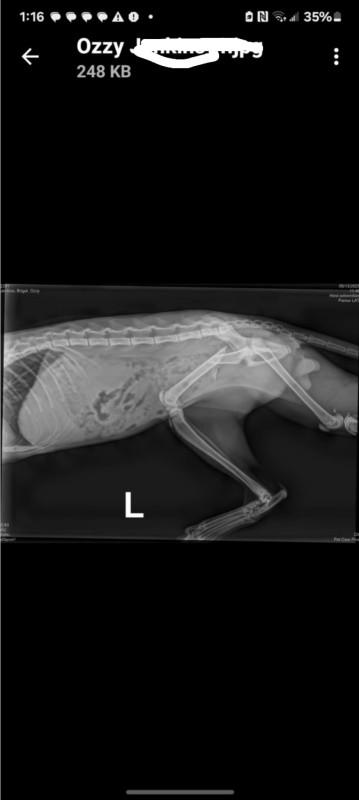

In a world where the bond between humans and animals is cherished, my seven-month-old kitten, Ozzy, has captured my heart with his playful spirit and affectionate nature. Recently, a tragic accident left him with a broken hip, a condition requiring immediate surgical intervention.

As a responsible pet owner, I am acutely aware of the importance of prompt medical care. Unfortunately, the cost of the surgery is significant, and without assistance, I wont be able to afford his surgery.